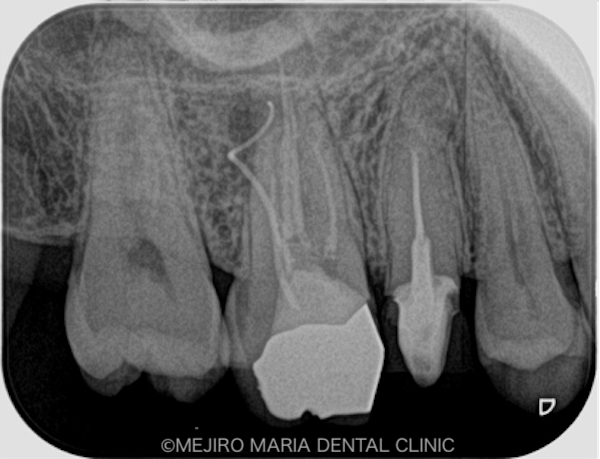

目白マリア歯科|ブログ|【症例】コンセプトを守った再根管治療(精密根管治療)|治療詳細1

右上6番の歯に確認できたフィステル(瘻孔)は、2回目の根管治療の際にはすでに消失していました。患者様のご希望により、すでに根管治療がされている手前側の歯(右上5番)も、根管治療をやり直すこととなりました。